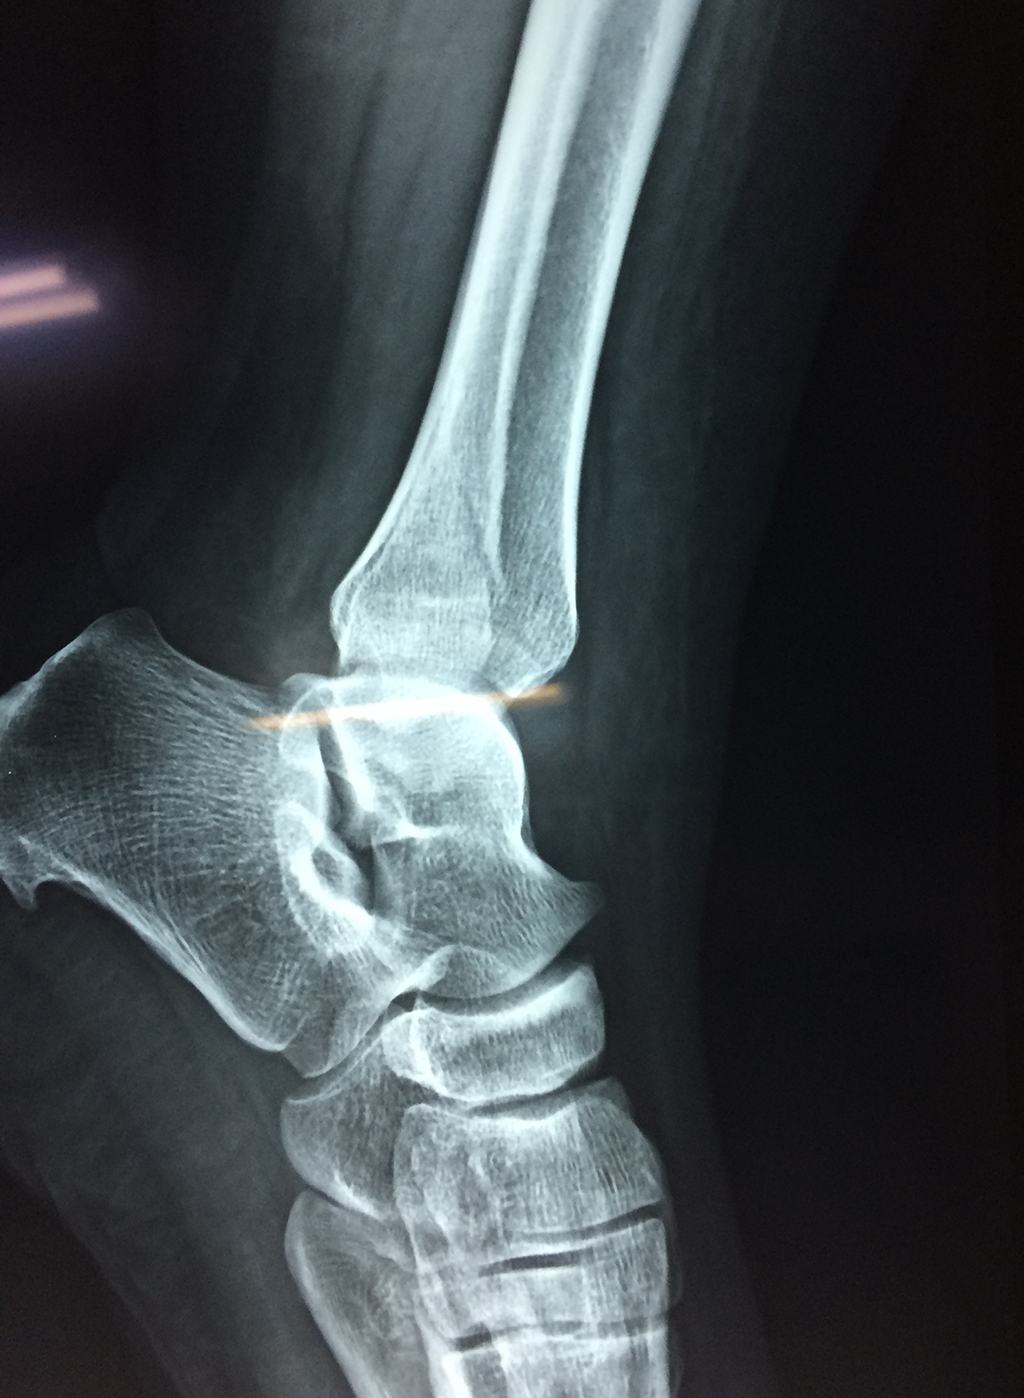

Una fractura de tobillo es la rotura de uno o más de los huesos del tobillo. Estas fracturas pueden ser:

Algunas fracturas de tobillo pueden requerir cirugía si:

- Los extremos de los huesos están desalineados entre sí (desplazados).

- La fractura se extiende hasta la articulación del tobillo (fractura intra-articular).

- Los tendones o ligamentos (tejidos que sujetan los músculos y los huesos entre sí) están rotos.

Cuando se necesita cirugía, es probable que esta implique el uso de clavijas de metal, tornillos o placas para sostener los huesos en su lugar mientras la fractura se consolida. Los elementos de soporte pueden ser temporales o permanentes.